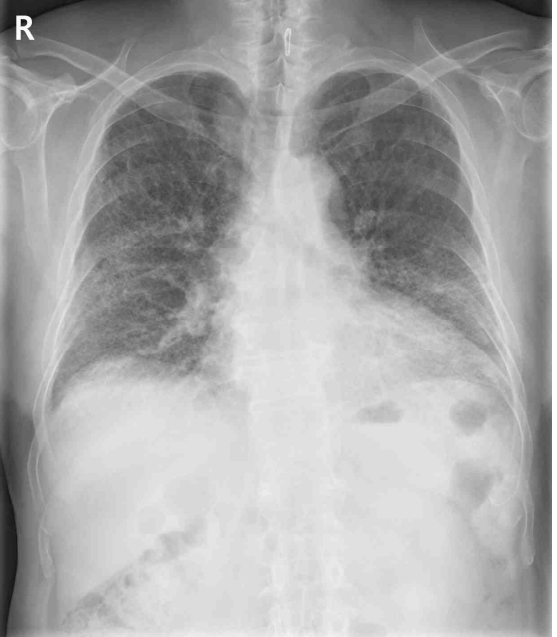

45세 남자가 6개월 전부터 기침이 심해지고 숨이 차서 병원에 왔다. 자동차 도장공으로 15년째 근무 중이고 비흡연자이다. 혈압 120/80 mmHg, 맥박 90/분, 호흡 20회/분, 체온 36.4°C이다. 가슴 X선사진과 가슴 컴퓨터단층촬영 사진이다. 검사 결과는 다음과 같다. 진단은?

CXR: Bilateral diffuse opacities

• CXR상 bilateral diffuse opacities가 관찰되며 chest CT상 양쪽 bilateral basal area에 fibrotic change를 시사하는 reticular opacities가 확인된다. 더불어 PFT상 제한성 양상으로, 영상소견과 폐기능 검사 소견을 종합하여 판단할 때 증상의 원인이 간질성 폐질환임을 알 수 있다.

• 간질성 폐질환 중 유기 화합물을 지속적으로 흡입하는 환자의 직업력을 고려하였을 때 가장 유력한 진단은 과민폐렴이며, 환자의 chest CT 소견 역시 이에 부합한다.